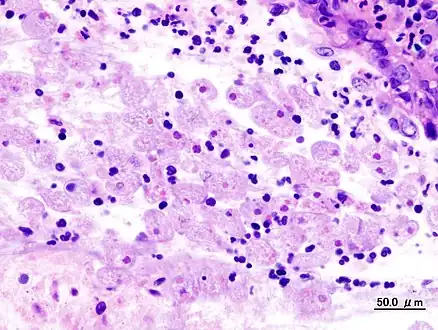

Amoebae in a colon biopsy from a case of amoebic dysentery.

Immunohistochemical staining of trophozoites (brown) using specific anti–Entamoeba histolytica macrophage migration inhibitory factor antibodies in a patient with amebic colitis.